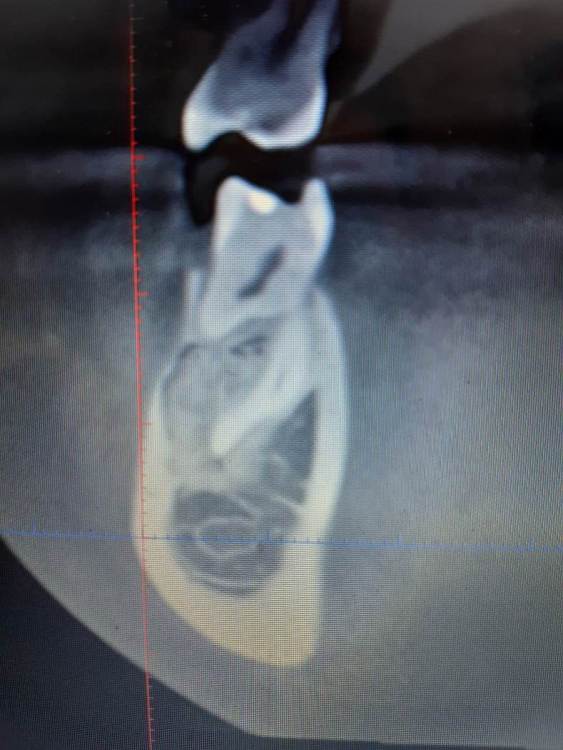

Коллеги, помогите советом что это может быть. Ничего не беспокоит, найдено случайно. Есть бруксизм, пат.стираемость, гнатолог считает что было неправильное ортодонтическое лечение.